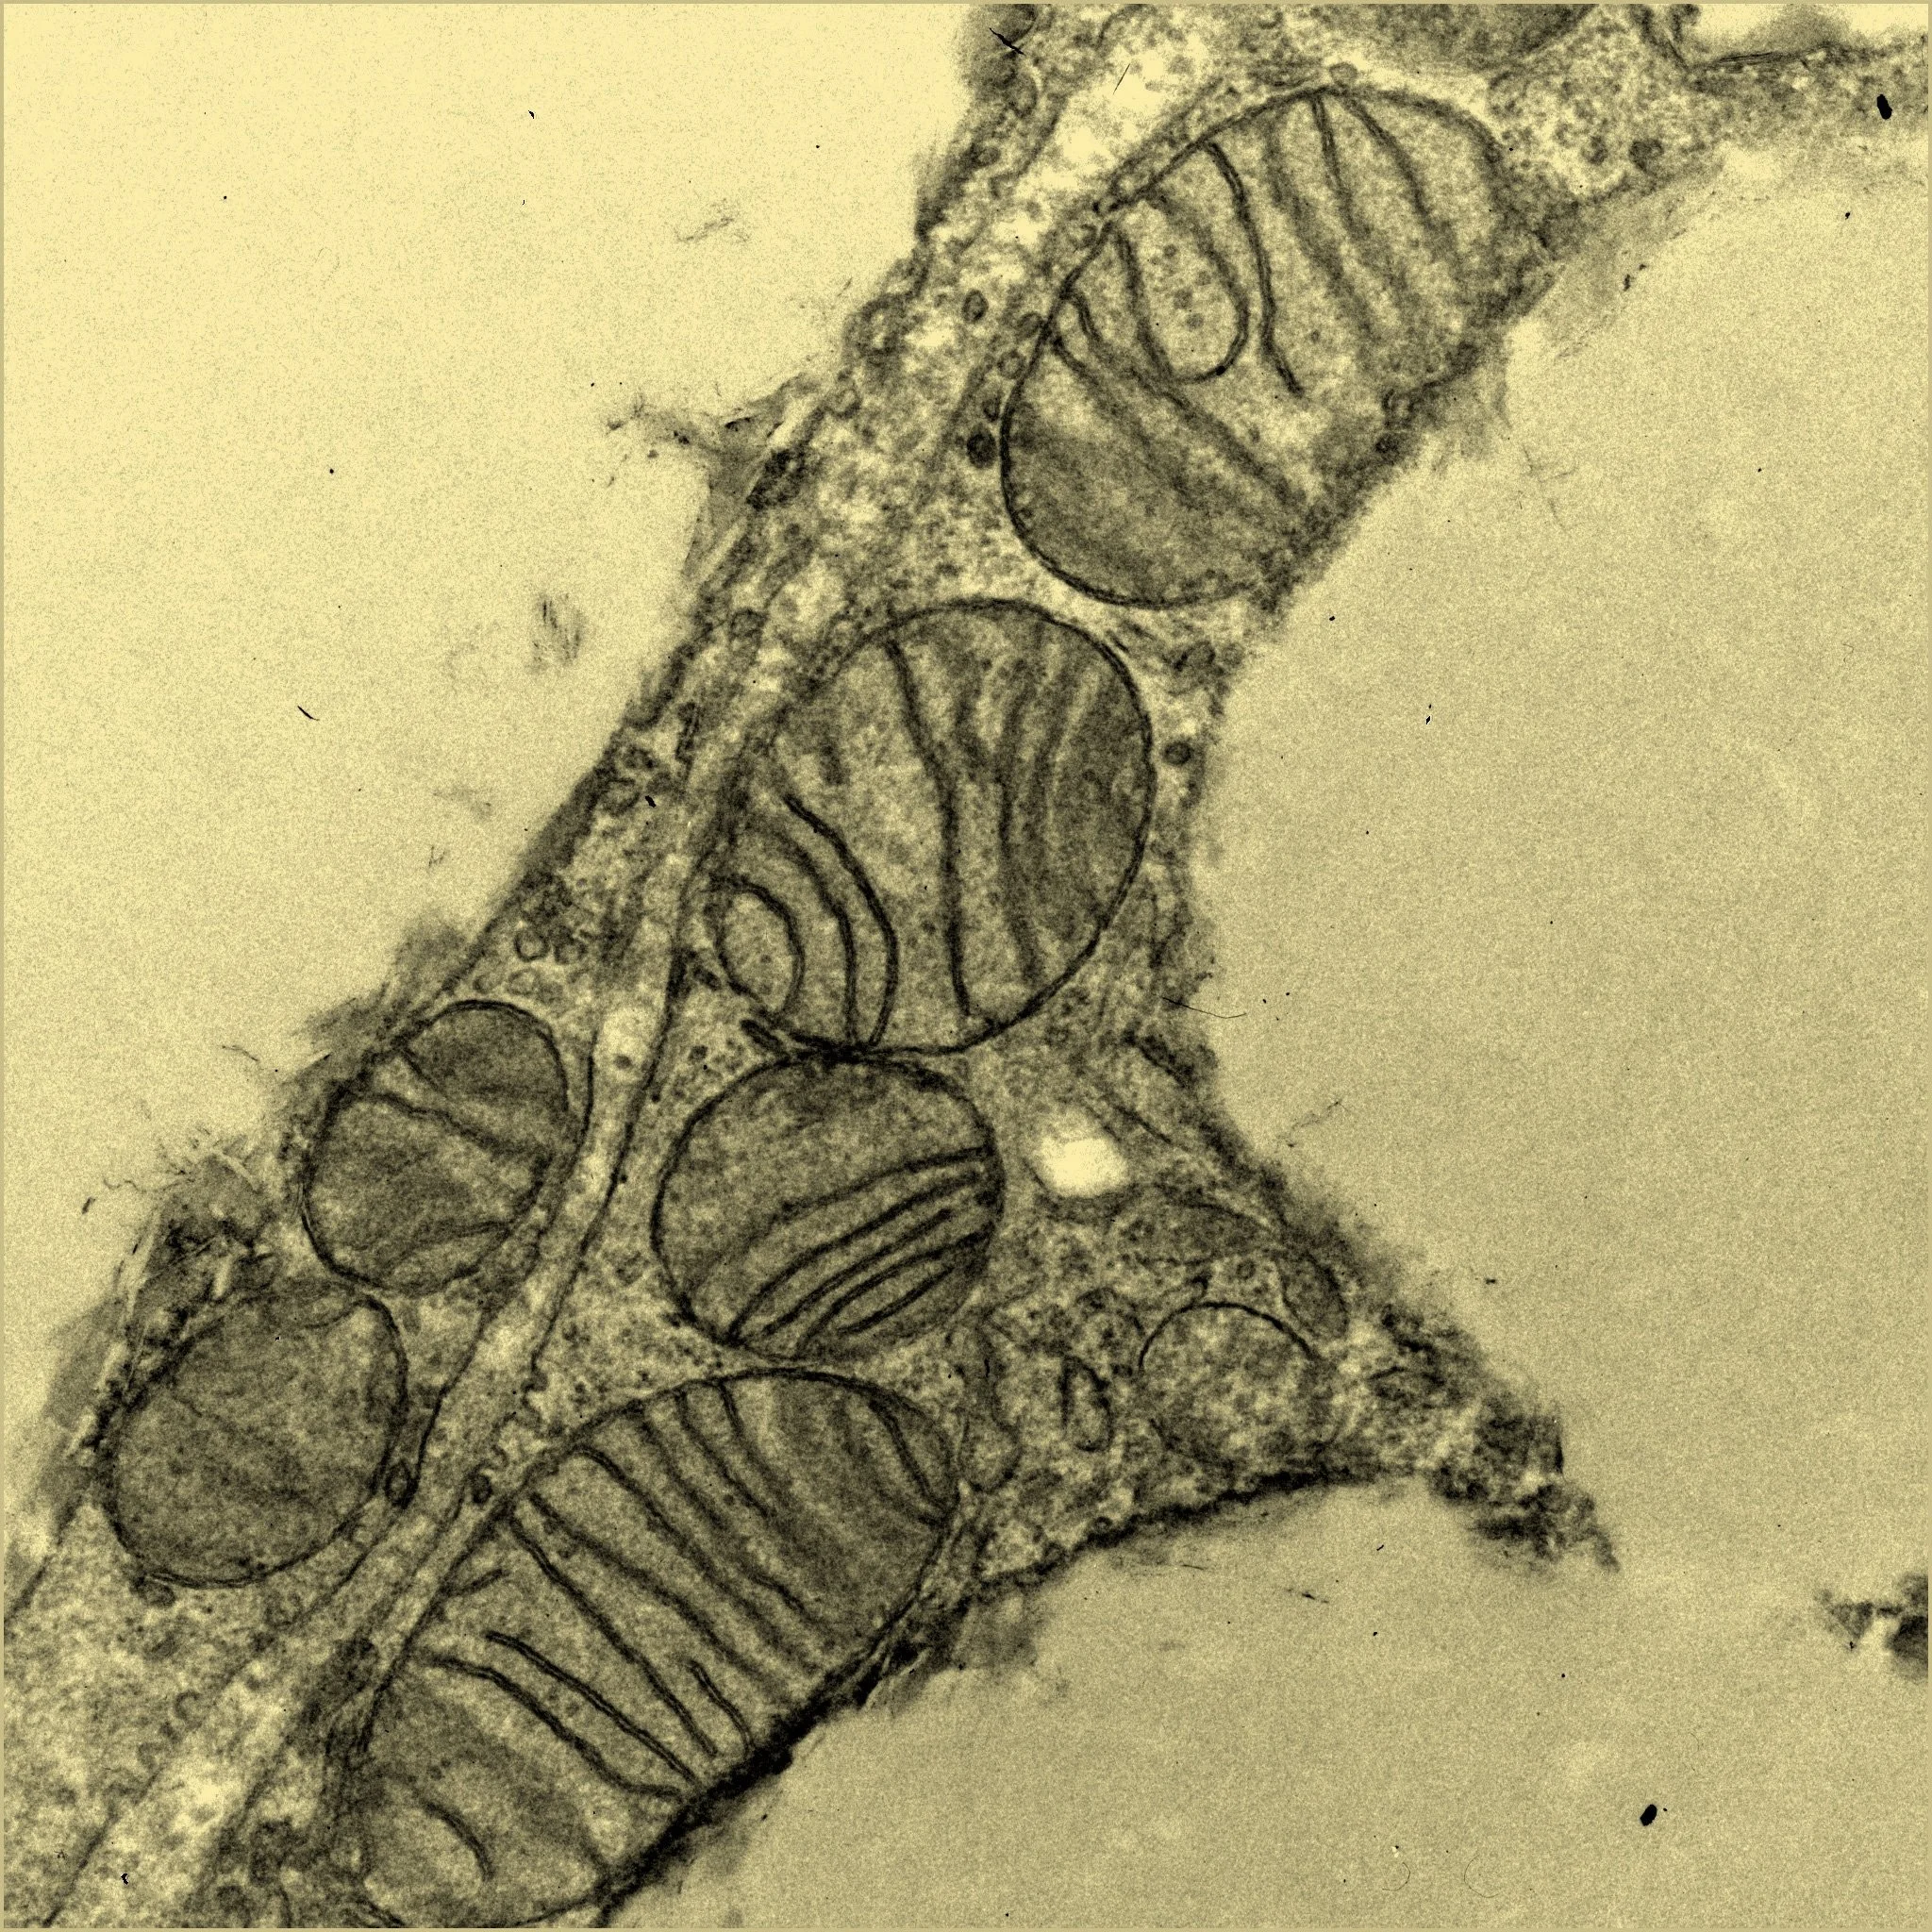

Mitocondrias en el tejido adiposo de ratones sin la microproteína SLC35A4-MP, que aparecen dañadas y disfuncionales. Cortesía: Salk Institute

El nuevo trabajo responde a esa pregunta con contundencia. Utilizando ratones modificados genéticamente mediante la técnica de cortapega genético CRISPR, el equipo eliminó la capacidad de producir SLC35A4-MP. A simple vista, los roedores manipulados parecían normales, pero bajo el microscopio su tejido adiposo marrón revelaba un panorama preocupante: mitocondrias agrandadas, menos numerosas y con forma anómala, incapaces de responder adecuadamente a situaciones de estrés energético como una dieta rica en grasas o la exposición al frío.